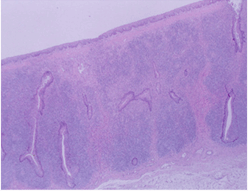

주요임상증상